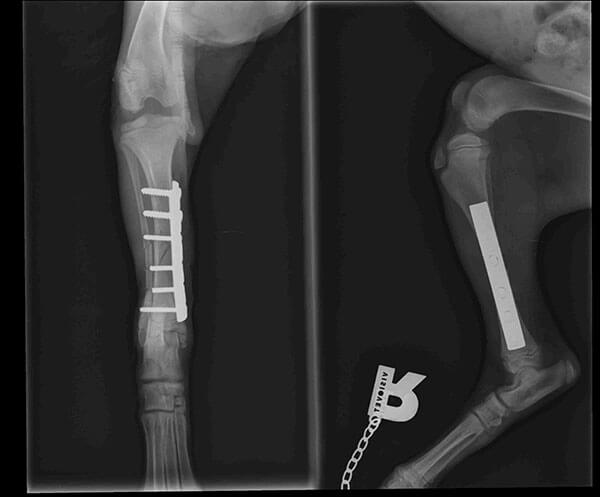

Baby Ray hatte Glück im Unglück, denn tierliebende Menschen haben ihn am Straßenrand liegend gefunden. Schnell war klar, dass Ray nicht laufen konnte, da sein Beinchen gebrochen war.

Natürlich wurde Ray so schnell wie möglich operiert. Die OP Kosten belaufen sich auf 240 €.